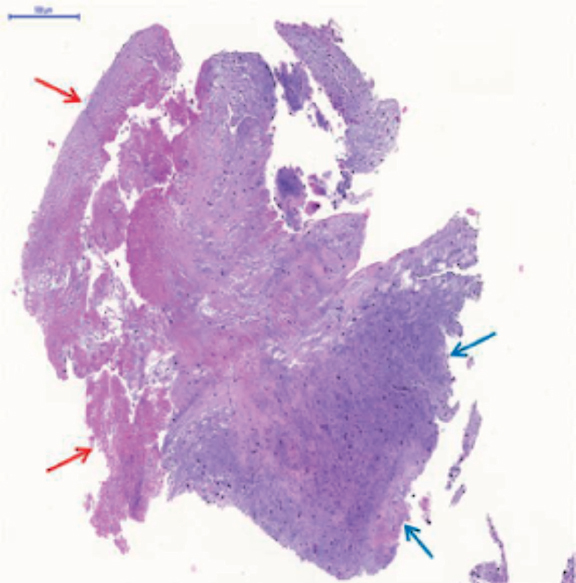

The evolution of the patient was not favorable, brain death was declared 24 h after admission, and the patient was eventually declared dead. The microscopic analysis of the coronary aspirate revealed the presence of mesenchymal tissue with myxoid changes consistent with tumor embolism (figure 1) whereas the macroscopic piece confirmed the diagnosis of atrial myxoma (figure 2, arrow).

Figure 2. Atrial myxoma, macroscopic piece.